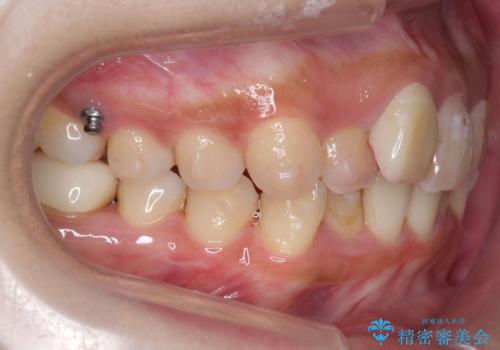

- 前歯のがたつきを主訴に来院。

保険治療の被せ物が前歯に2本あり、矯正治療で移動後にセラミックでやり替えを行っています。

右上のかみ合わせがずれていたため、インプラント矯正を行い、奥歯を後ろに下げて治療しています。